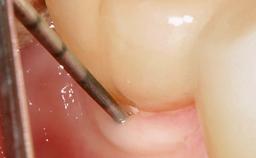

In this case, Myroslav Solonko, Ignacio Sanz Sánchez and Mariano Sanz present a treatment that aims to eliminate exposed implant threads by modifying the implant surface, converting a moderately-rough surface into a smooth surface.